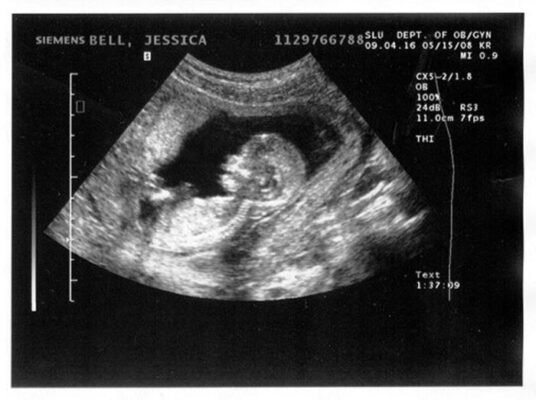

Ультразвукове дослідження (УЗД)

Технології роблять дива, друзі! УЗД дозволяє побачити і почути те, що ще недавно було неможливим. І це не просто картинки — це ваш шлях до кращого розуміння того, як росте і розвивається ваше маля.

- Перший візит: Якщо вам щастило, перше УЗД покаже серцебиття дитини. Це момент, який забути неможливо.

- Другий візит: Більш детальне уявлення, де можна перевірити ймовірні ускладнення.

- Третій візит: Підтвердження терміну пологів і остаточні приготування.